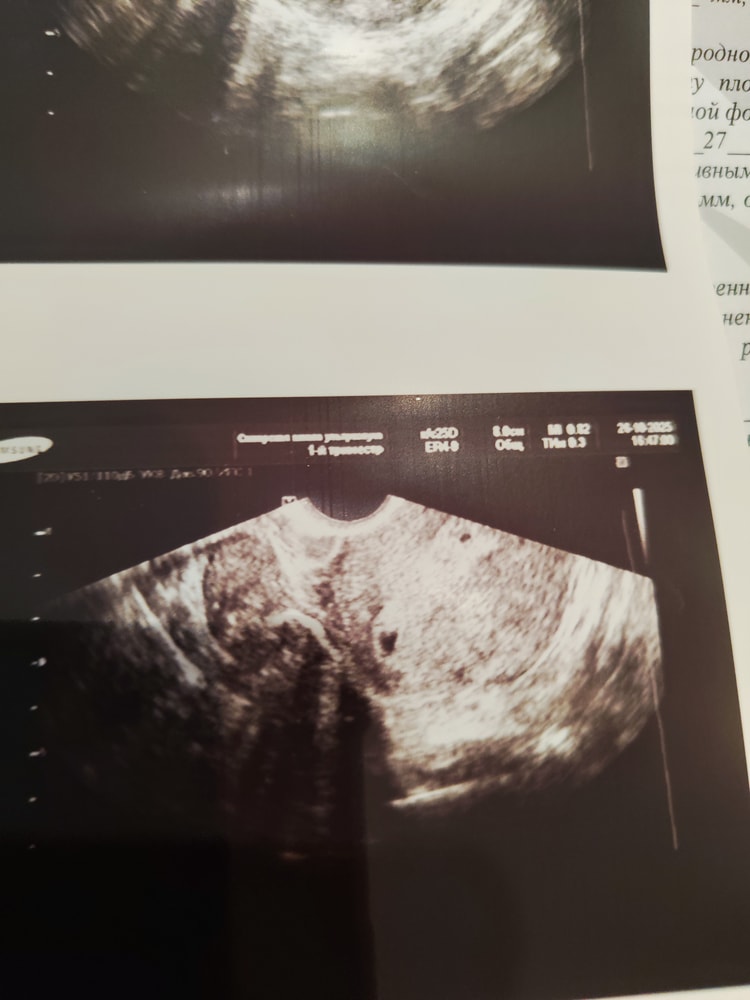

На узи срок 4 нед 2 яйца, одно 2 мм, второе 3 мм ( ложное? ) с жидким содержимым, желтое тело 1, фолликула 2.

ВВживую эти 2 черные точечки на узи больше конечно, это неудачное фото